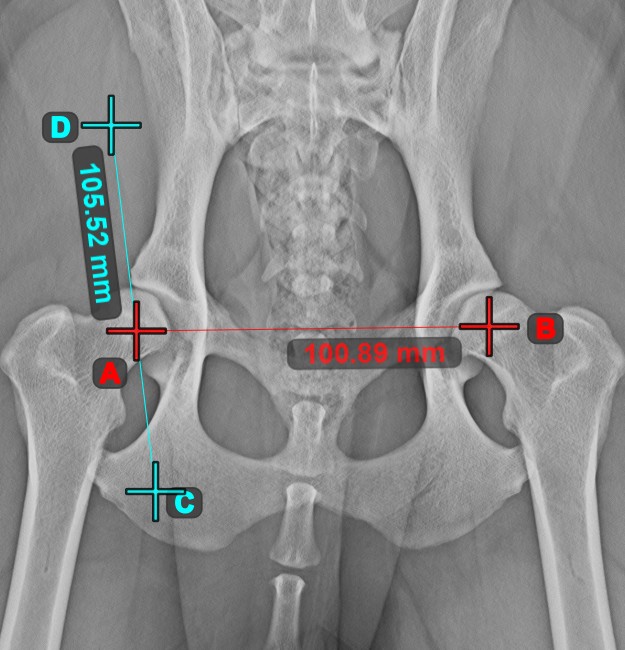

Line Measurement

Create a line measurement to calculate the distance between two points with high precision.

Select the Line Measurement tool and assign it to one of the available mouse buttons. Place the start and end points on the scene or select them from already existing points on the image. The distance between the two points will be automatically calculated by using the default calibration data, or the recalibrated data by the length calibration measurement.

Modify the start and end point by using the Select/Move Item tool. The distance between the two points will be automatically recalculated.